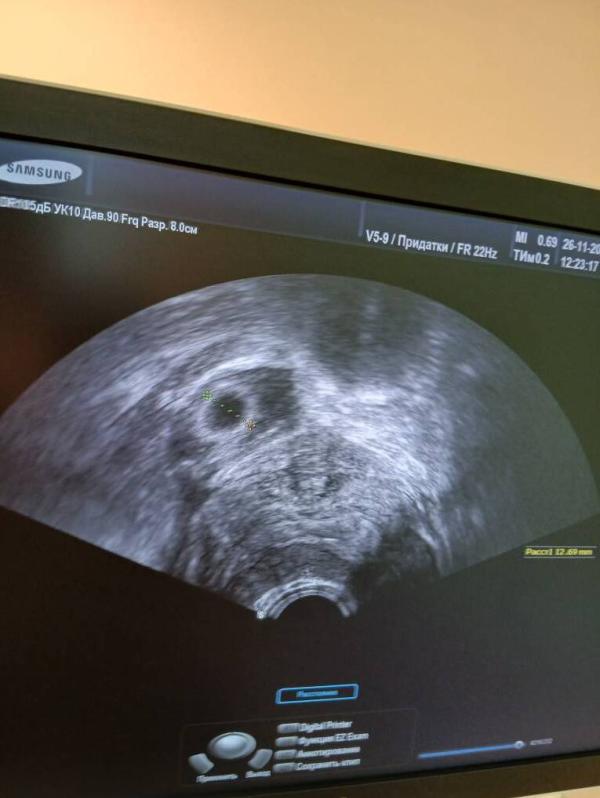

Ну вот девочки 14 лет ожиданий удалось с первой попытки эко,лежу неделю на сохранении хгч хорошо удваивается,но столько радости развеяли на прах обнаружили внематочную беременность на 7 неделе и ещё пя 2.7 в матке даже невериться что это случилось на душе так больно.Сегодня будут делать операцию мне так плохо😭😭😭😭

Так перенос был одного эмбриона, а беременностей 2, если я правильно понимаю. В матке то, что перенесено, а в трубе естественная беременность 😔